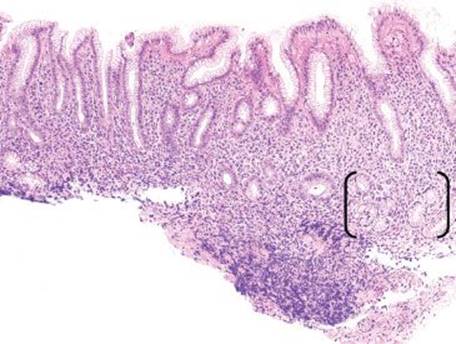

Figure 2.98 Chronic gastritis pattern, basal lymphocytic infiltrate subpattern, AMAG. At scanning magnification, this tissue fragment shows a chronic inflammatory infiltrate that is bottom-heavy (arrow). Whereas this pattern in the body/fundus suggests AMAG, this finding in the antrum suggests EMAG. Awareness of the compartment is critical for determining the underlying etiology of the chronic gastritis pattern.